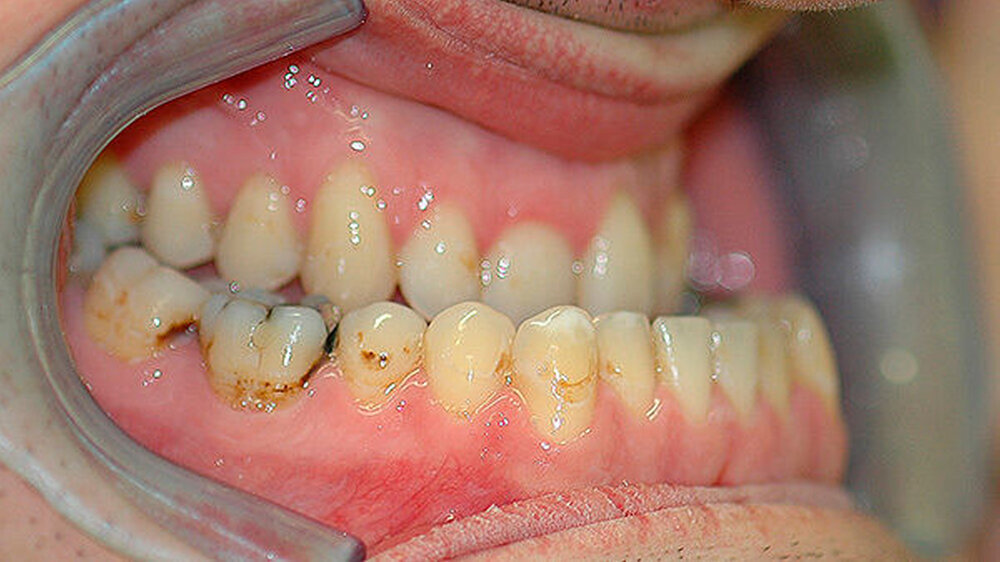

Der Fall: Progenie durch Akromegalie

Der Patient stellte sich erstmals 2010 in der Stuttgarter MKG-Spezialsprechstunde vor. Im ersten Schritt wurde der Tumor an der Hirnanhangdrüse über die Nase entfernt. In interdisziplinärer Zusammenarbeit mit einem Fachzahnarzt für Kieferorthopädie wurden im ersten Behandlungsabschnitt die Zahnbögen ausgeformt. Um den Oberkiefer in der Breite zu dehnen, führten die Stuttgarter Zahnärzte im Oktober 2012 eine chirurgisch unterstützte Gaumennahterweiterung durch.